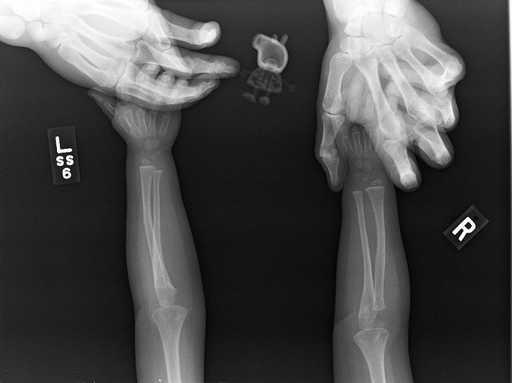

1. 「我女儿坚持要佩奇陪她才要拍X光。」

一些奇怪的X光照片,看完整个人都不好了……-1.jpg